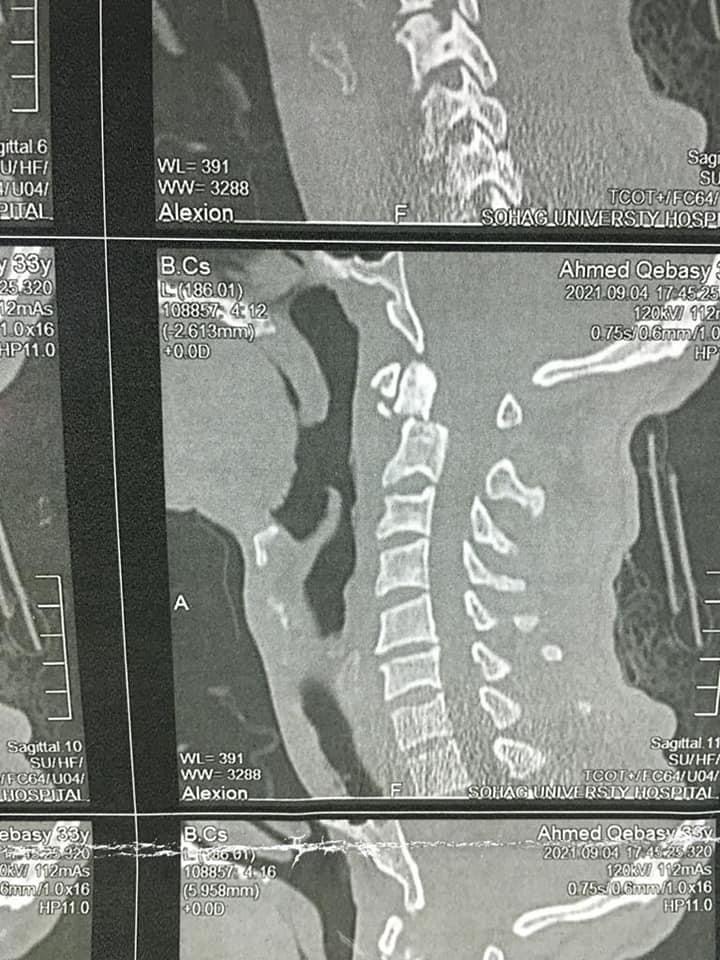

صرح الدكتور مصطفى عبد الخالق القائم بأعمال رئيس جامعة سوهاج، بأن فريق طبي متخصص من قسم جراحة العظام بالمستشفى الجامعي نجح في إجراء عملية جراحية لتثبيت كسر بالفقرة العنقية الثانية لشاب في العقد الثلاثين من عمره، بواسطة التدخل الجراحي من الأمام.

وقال عبد الخالق، في بيان، اليوم الأحد، إن تلك الجراحة تعد من أكثر جراحات العمود الفقري خطورة نظرا لقربها من قاع المخ والحبل الشوكي وتحتاج لدقة ومهارة عالية في إجراؤها.

وبعد إجراء الفحوصات والإشاعات اللازمة للمريض تبين وجود كسر في الفقرة الثانية من العمود الفقري الرقبي، ويحتاج إلى جراحة عاجلة لتثبيت الفقرة العنقية.